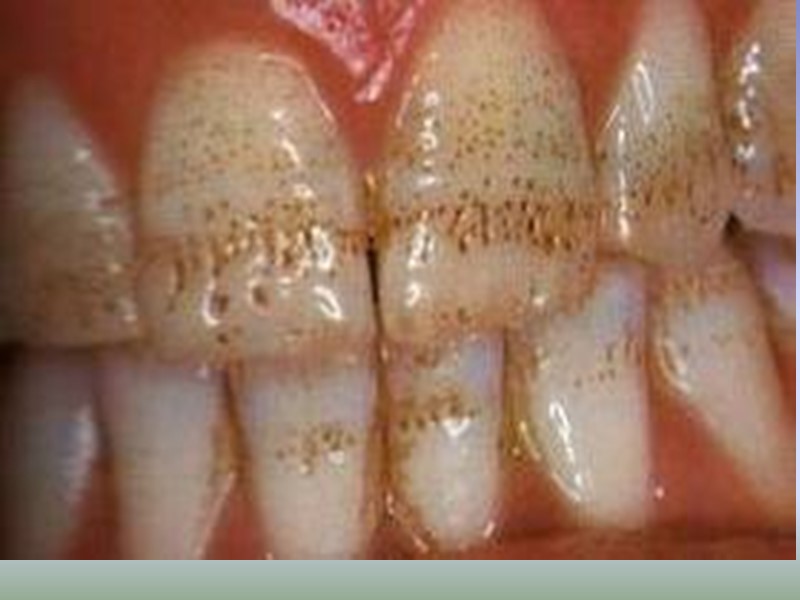

Классификация по локализации: Фиссурный кариес. Контактный (апроксимальный) кариес. Пришеечный (цервикальный) кариес. Циркулярный (кольцевой) кариес.

Клинические проявления кариеса зубов Кариес в стадии пятна (macula cariosa). Жалобы на боль, как правило, отсутствуют. В области пятна в отдельных случаях может появиться ощущение повышенной чувствительности к химическим раздражителям (кислое, соленое, сладкое). Если белое или пигментированное пятно расположено на вестибулярной поверхности фронтальной группы, то пациент может предъявлять жалобы эстетического порядка.

Диагностика начального кариеса Объективно: на поверхности эмали видно чаще одиночное меловое или пигментированное пятно диаметром 3-5 мм. Наиболее часто кариозные поражения локализуются в естественных углублениях зуба (фиссурах), контактных поверхностях, в пришеечной области.

Поверхностный кариес (caries superficialis). жалобы на кратковременную боль от химических раздражителей (сладкого, соленого, кислого) температурные раздражители редко вызывают боль может протекать бессимптомно.

Поверхностный кариес (caries superficialis). При объективном исследовании обнаруживается кариозная полость в пределах эмали с неровными шероховатыми стенками и дном. Зондирование дефекта эмали может быть болезненно, зонд погружается в размягченную эмаль на незначительную глубину. Пульпа зуба при поверхностном кариесе реагирует на ток силой 2— 6 мкА.